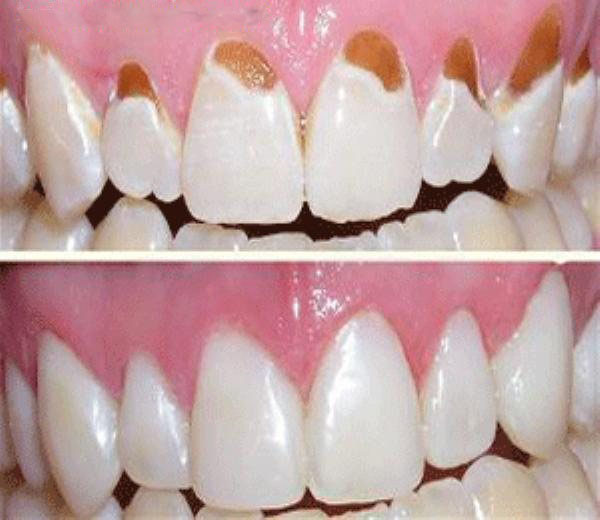

В соответствии с принятой классификацией принято выделять три основных вида эрозии:

- Страдают только наружные слои эмали, а дефект чашеобразной формы имеет белесый оттенок;

- Эмаль поражена на всю толщину до дентина;

- Патология затрагивает слой дентина, и выявляется пигментация (цвет эрозии варьирует от светло-желтого до коричневого).

Лечение эрозии эмали подразумевает активную реминерализующую терапию. Она включает процедуры аппликаций кальция и фосфора и электрофорез с растворами кальция. По окончании курса проводится покрытием зубов фторлаком или фторгелем. Также показан прием внутрь минеральных препаратов и витаминных комплексов на протяжении 2-3 недель (на усмотрение врача). При выраженном косметическом дефекте ставится вопрос о пломбировании дефекта современными композитными материалами или изготовлении ортопедических конструкций – коронок, покрывающих всю поверхность больного зуба. Альтернативой коронкам являются виниры – тонкие пластинки, которые врач фиксирует на вестибулярную поверхность зуба. Такой метод лечения позволяет добиться «голливудской улыбки» даже при запущенном некариозном поражении.

Критерием качества проведенной терапии начальных форм эрозии эмали является сглаживание дефекта и исчезновение болевого синдрома при воздействии химических и термических раздражителей. При лечении более запущенных форм заболевания, предполагающих заполнение дефекта композитом, пломба должна быть незаметной, т. е. соответствовать по цвету окружающим здоровым тканям.

Как выглядит эрозия зуба?

Эрозия зубов представляет собой кругообразный либо овальный дефект эмали, который расположен в максимально выпуклой области вестибулярной поверхности коронковой части в поперечном направлении. Ее основание достаточно гладкое, твердое и блестящее.